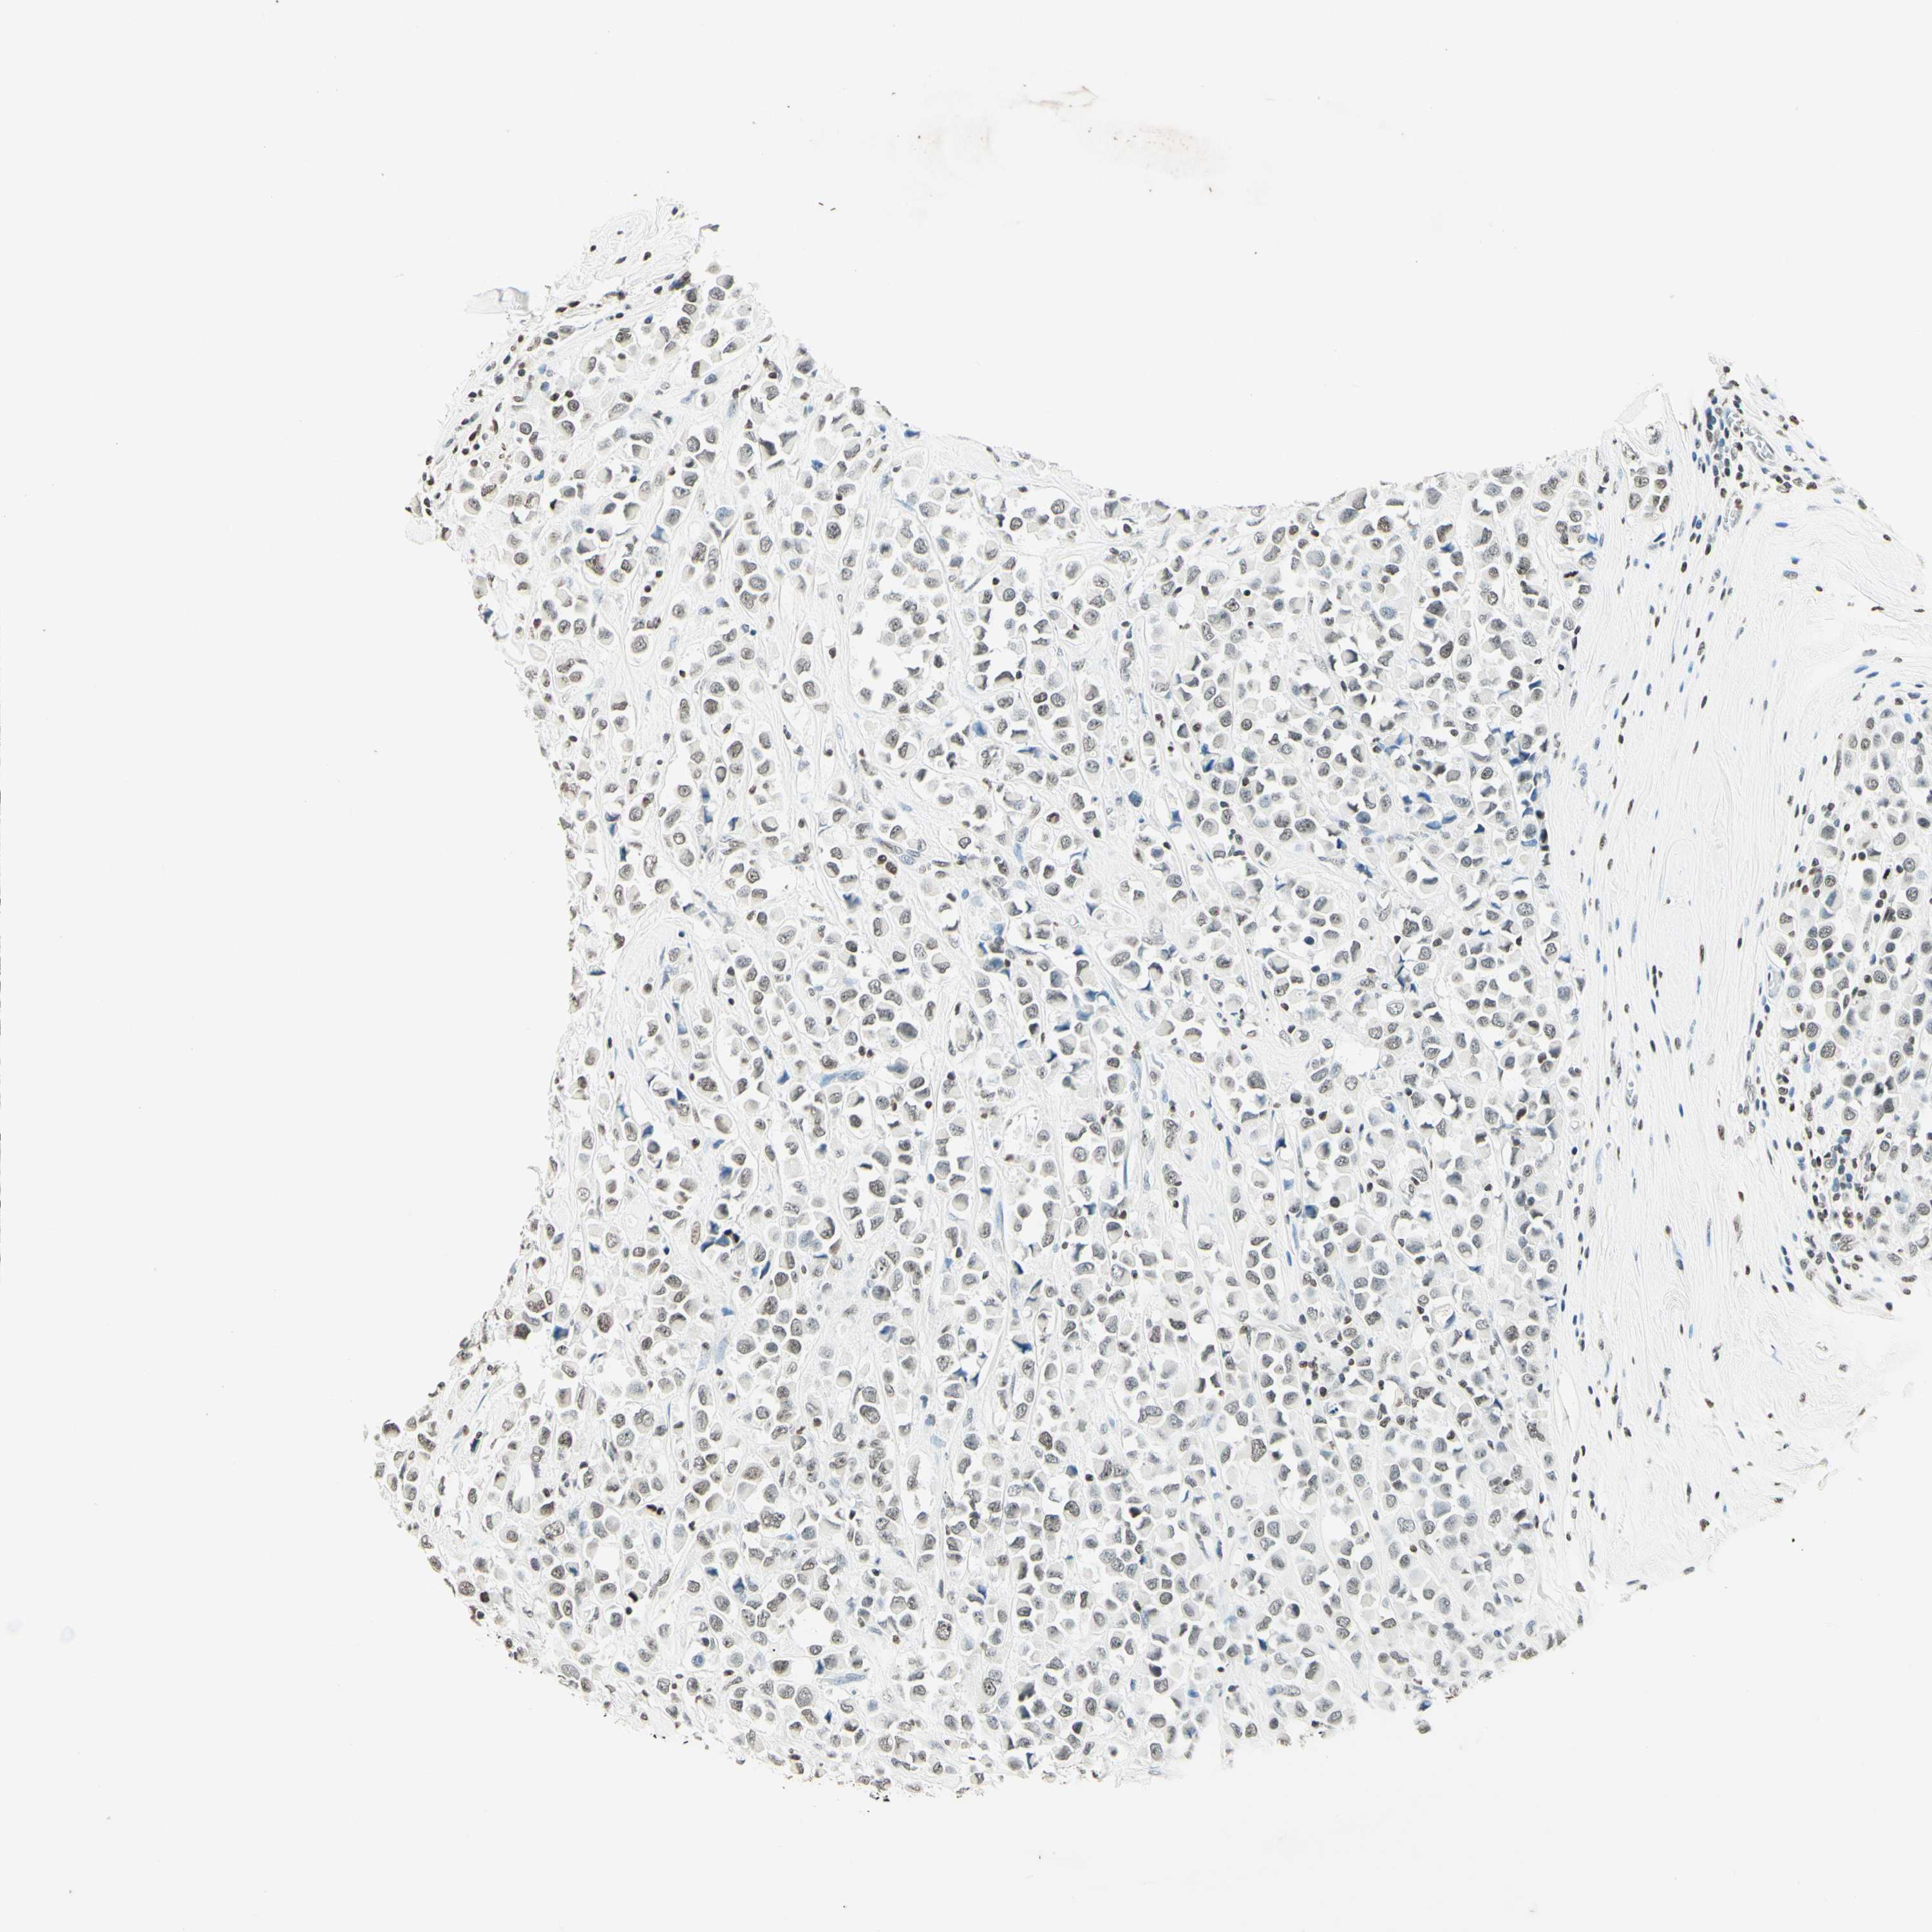

BRCA TCGA BRCA VALIDATION PROTEIN EXPRESSION